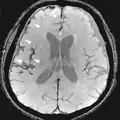

| Fluid-attenuated inversion recovery | FLAIR | Fluid suppression by setting an inversion time that nulls fluids | High signal in lacunar infarction, multiple sclerosis (MS) plaques, subarachnoid haemorrhage and meningitis (pictured).[15] |

| |